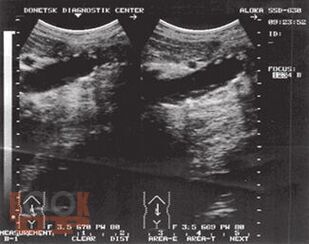

Монография является пятой и заключительной книгой серии «Хроническая абдоминальная боль». Автор представила основные причины боли при заболеваниях других органов и систем, которые могут проявляться абдоминальной болью. Особое внимание уделено патогенезу, клинической характеристике и дифференциальной диагностике болевого синдрома, а также лечению.